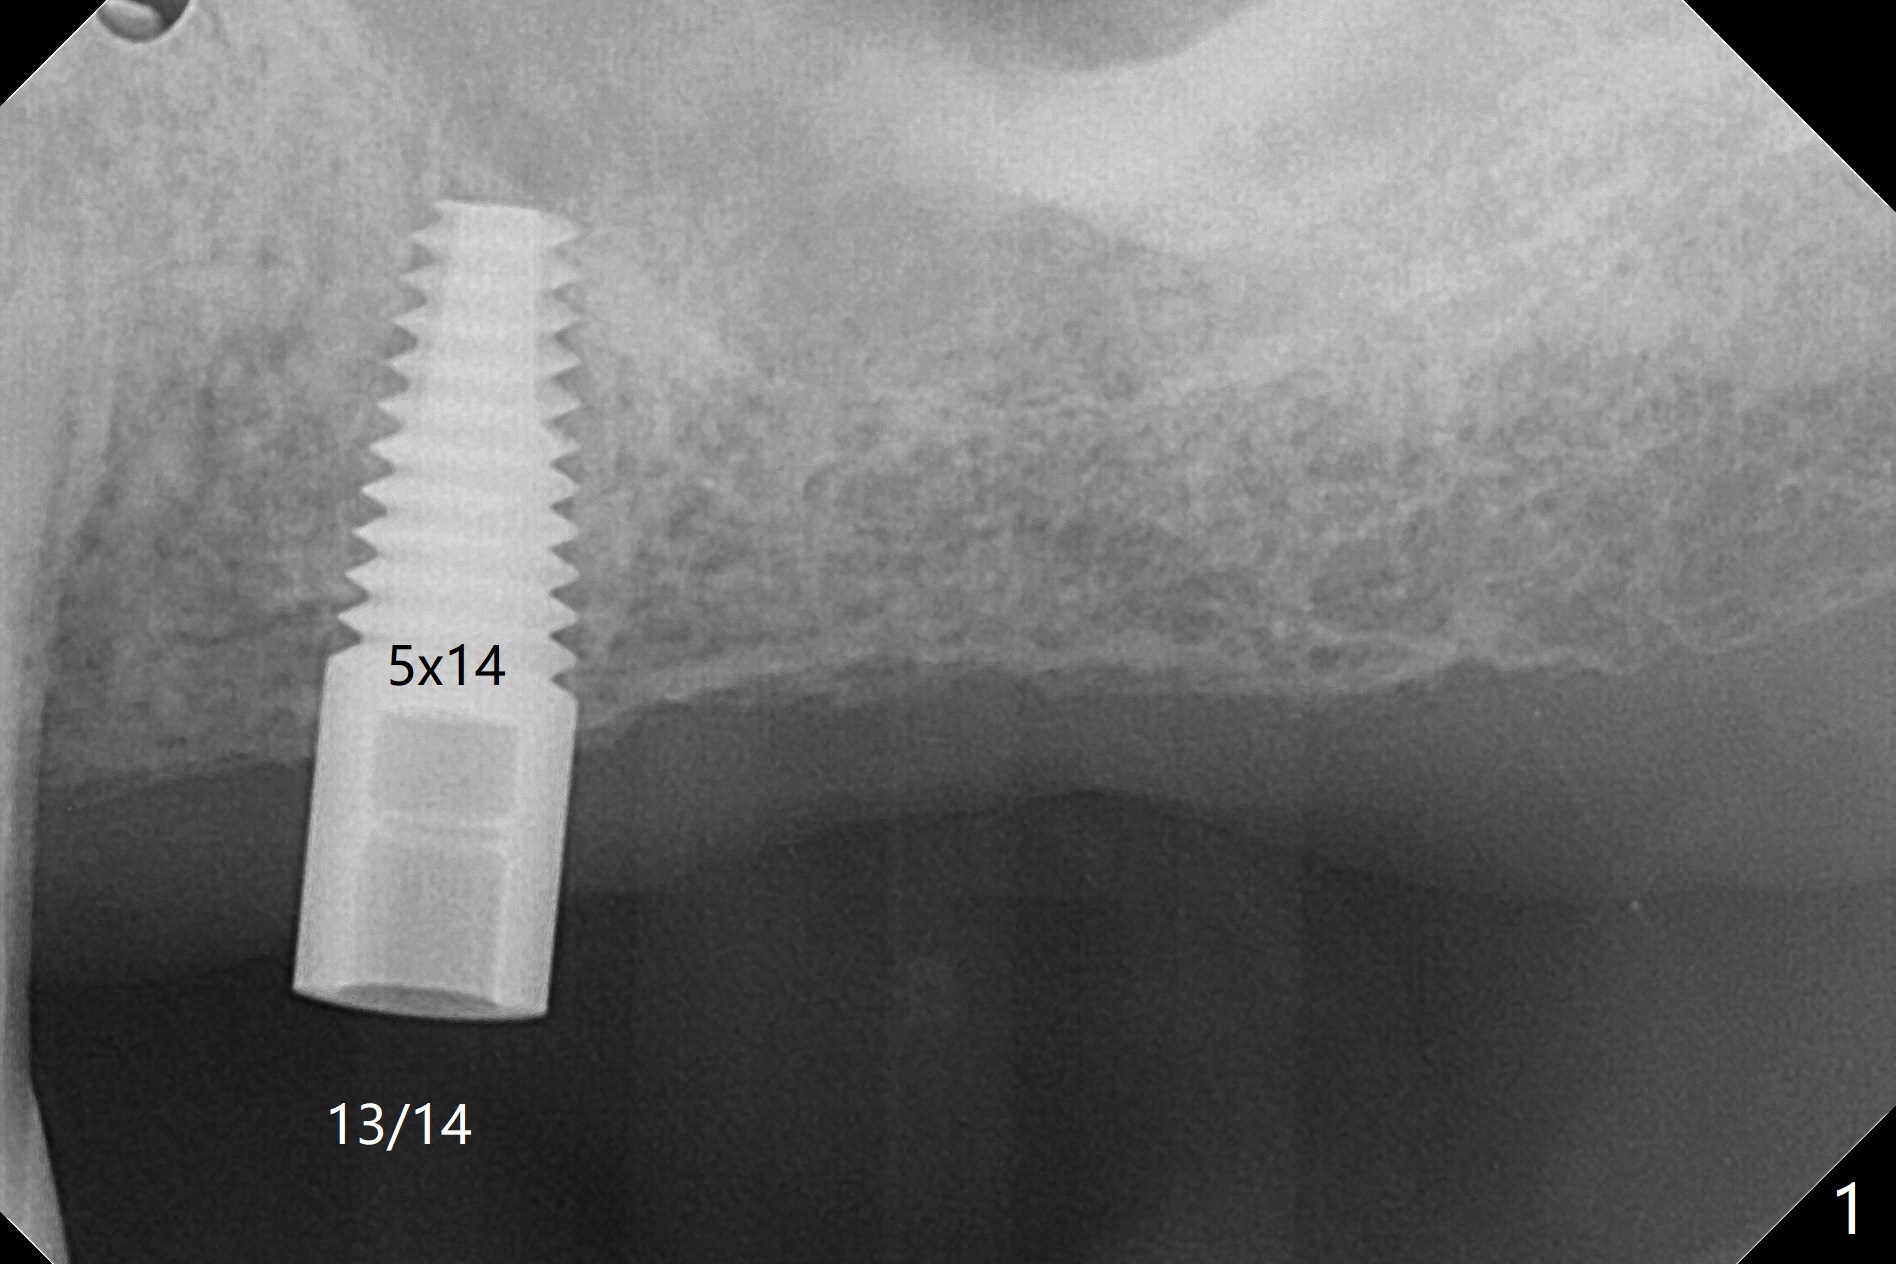

Implant Placed at 2nd Premolar Will be Used As a Molar

Guide designed for a 5x10 mm bone-level implant is used to place a tissue-level one (Fig.1) after 3.5x11.5 mm and 4.0x10 mm drills with 10.5 mm offset.